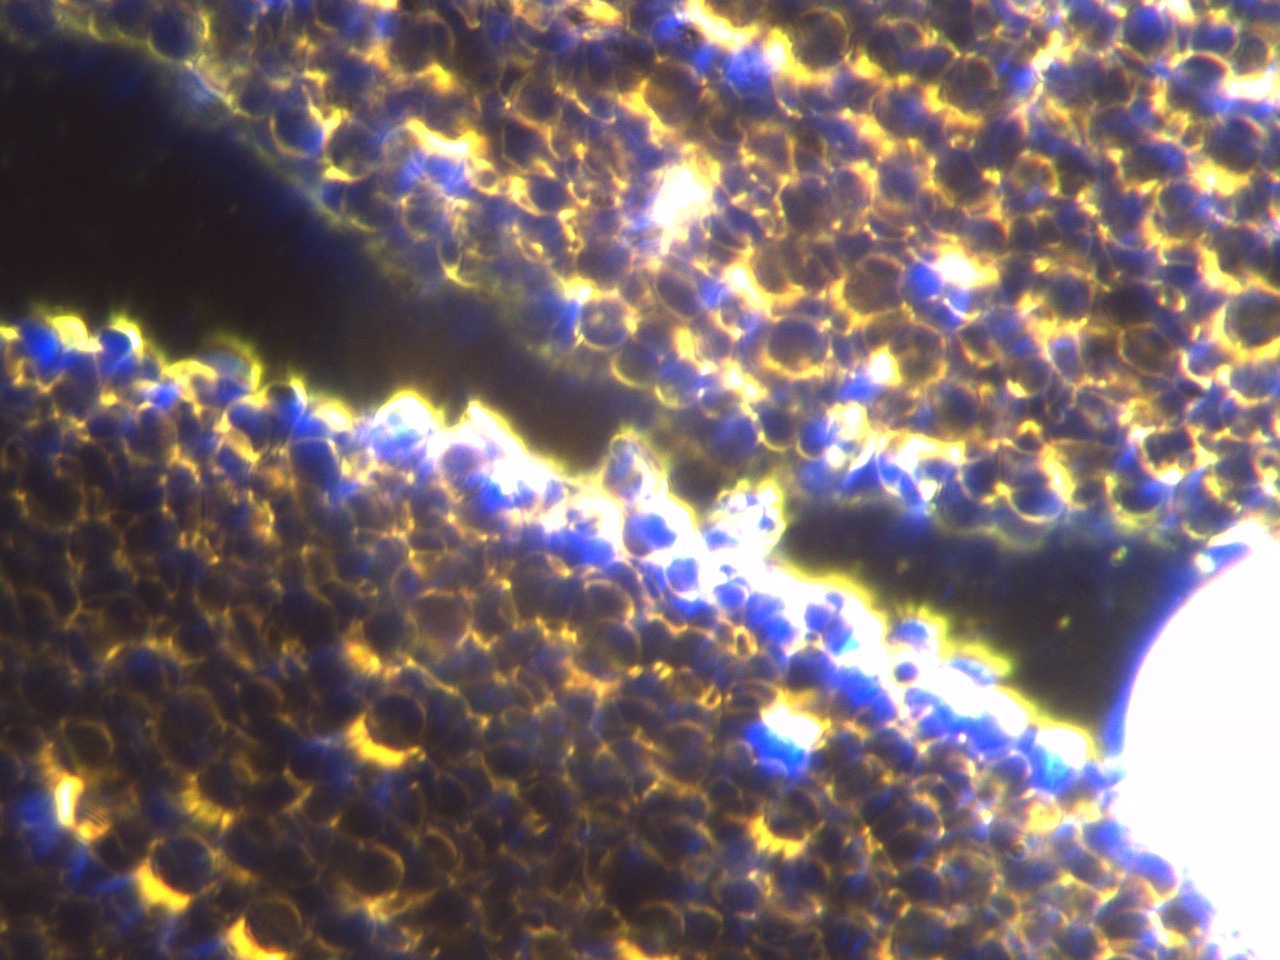

Ida zeigt eine hochgradige chronische Ohrentzündung (Otitis externa) und Hautausschlag. Zur Abklärung der Ursache haben wir allgemeine Blutuntersuchungen, Dunkelfeldanalysen, Hautgeschabsel, Tupferproben der Ohren, sowie einen Blut-Allergietest durchgeführt. In der allgemeinen Blutuntersuchung zeigt Ida dickes Blut und hohe Globulinwerte (Hinweis auf eine Allergie). In der Dunkelfeldanalyse (Fluoreszierendes Mikroskop durch das man einen Einblick in das lebendige Blut erhält) zeigt die Hündin eine starke Übersäuerung (Säureblasen), dickes Blut (Histaminose) und ein überlastetes Immunsystem (zugrunde gegangene weiße Blutkörperchen = Symblasten).

Histamine sind Gewebs- und Abwehr-Hormone, welche bei zu stark sensibilisierten Organismen zu viel gebildet werden und zu wenig von einem inaktiven Darmsystem und den Nieren ausgeschieden werden. Dies hat einige Auswirkungen: Das Blut wird schwerfähig, die kapilläre Durchblutung und damit die Sauerstoff- und Nährstoffversorgung wird beeinträchtigt. Im Hautgeschabsel sehen wir Malassezia Pilze (Hefepilze – meist sekundär zu einer Allergie). Die Tupferproben der Ohren ergeben die Besiedelung mit vorwiegend resistenten Keimen (Pseudomonaden und Enterokokken). Der Allergietest ergibt eine Allergie auf Rind und Soja, sowie auf Milben, Pollen und Flohspeichel. In der Ausdifferenzierung der Milben wird deutlich, dass Ida eine Hausstaubmilben- und Futtermilbenallergie zeigt. Zusammenfassend zeigt der Basset eine Ohrentzündung und eine Atopische Dermatitis (Hautentzündung) durch eine Malasseziainfektion.

Die Symptomatik von Idas Haut ist nach dieser Behandlung nahezu vollständig verschwunden. Einzig und allein das Ohr macht uns noch aufgrund der resistenten Keime und der starken Hängeohren der Bassets zu schaffen. Eine Besserung konnten wir bereits erzielen, eine Heilung ist noch zu erwarten. Unseren Therapieerfolg erkennen wir nicht nur in Idas verbesserter Symptomatik, sondern auch in der Kontrolle der Dunkelfeldanalyse.